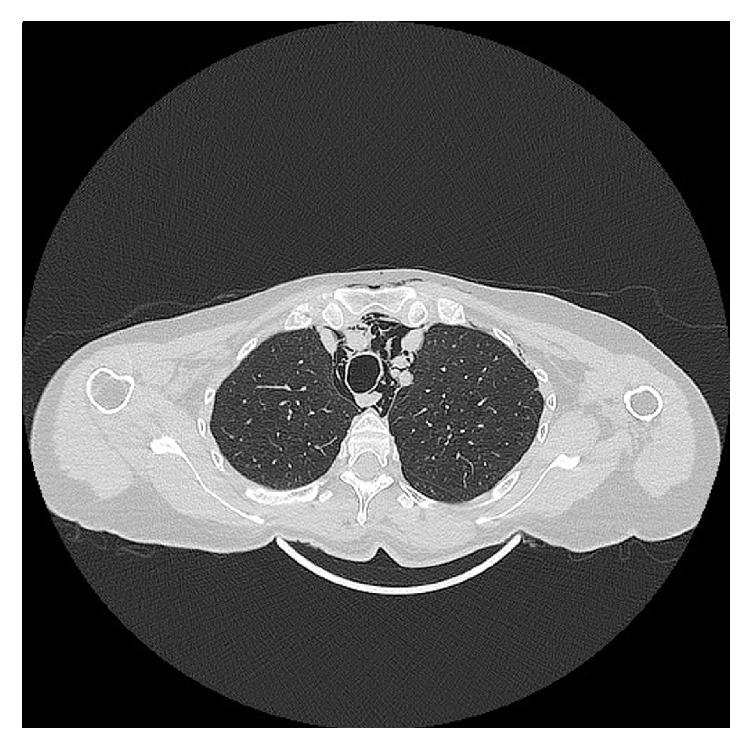

Subcutaneous emphysema is rare during or after dental procedures (usually extractions). Here, we describe the case of a 65-year-old woman who developed massive cervicothoracic subcutaneous emphysema and pneumomediastinum during a dental hygiene procedure employing an artificial airflow. She was diagnosed based on clinical manifestations and computed tomography (CT). CT revealed massive subcutaneous emphysema extending from the superior left eyelid to the diaphragm. We describe the clinical and radiological characteristics of this rare case.

皮下气肿在牙科手术期间或术后(通常为拔牙)较为罕见。在此,我们描述一例65岁女性的病例,该患者在一次使用人工气流的口腔卫生护理过程中出现了广泛的颈胸部皮下气肿和纵隔气肿。根据临床表现和计算机断层扫描(CT)对其进行了诊断。CT显示广泛的皮下气肿,范围从左上眼睑延伸至至膈肌�至膈肌。我们描述了这一罕见病例的临床和放射学特征。